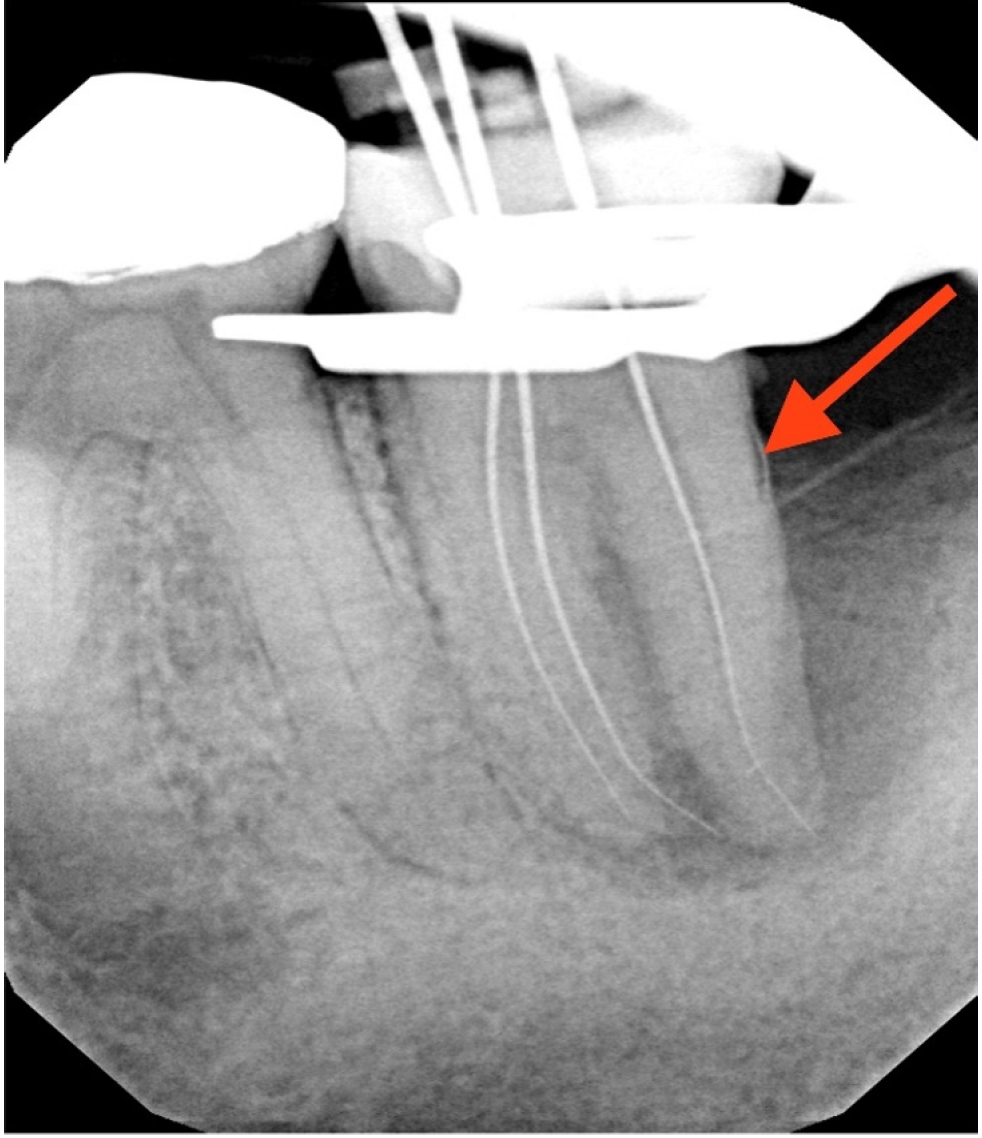

At the 2-week follow-up, the sinus tract had healed. After the same anesthesia and isolation protocol as the first visit, the tooth was accessed through the temporary restoration. Calcium hydroxide was irrigated out with 17% ethylenediaminetetraacetic acid solution, which was ultrasonically activated for 15 seconds in each canal. This was followed by 5% sodium hypochlorite irrigation, which was ultrasonically activated for 15 seconds in each canal, after which cone fit was verified clinically and confirmed with a radiograph (Figure 3). The canals were then dried with paper points, and obturation was completed using gutta-percha cones and AH Plus sealer (Dentsply DeTrey GmbH, Konstanz, Germany) with the cold lateral condensation technique. The tooth was temporized with a sterile sponge and Cavit (3M ESPE) and a postoperative radiograph was captured (Figure 4). A referral for periodontal therapy was given to the patient.

The patient reported for the periodontal treatment after 2 months. At this time, periapical radiograph (Figure 5) indicated reduced periapical radiolucency, but the radiolucency on the distal aspect of the distal root persisted. The tooth was nontender to percussion, but an 11 mm pocket was present along the distal-buccal line angle.

Figure 2.

Working length radiograph showing radiopaque fragment consistent with a cemental tear along distal root (red arrow).

rde-2025-50-e31f2.jpg

Figure 2. Working length radiograph showing radiopaque fragment consistent with a cemental tear along distal root (red arrow).